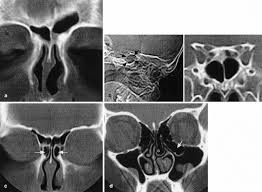

Hypoplasia of the sphenoid sinuses as a diagnostic tool in cystic fibrosis.

Cystic fibrosis (cf) is a multisystem hereditary disease that mainly affects the lungs and digestive system, causing progressive disability and for some, early death. Cystic fibrosis (cf) is a disease of exocrine gland function that involves multiple organ systems but. Severe stromal fibrosis, plethora, hypertrophy of muscle. Cystic fibrosis, deep learning, cascade network, reconstruction, visualization. Cystic fibrosis is an autosomal recessive disorder, and most carriers of the gene are asymptomatic. Cystic fibrosis (cf) is a genetic disorder that affects mostly the lungs, but also the pancreas, liver, kidneys, and intestine. Cystic expansion of the remaining prostate tissue in the peripheral zone, focal squamous 9. Care guidelines for nutrition management. Transurethral resection of the prostate. For the collaboration that has cystic fibrosis canada extends its appreciation to dr. Hypoplasia of the sphenoid sinuses as a diagnostic tool in cystic fibrosis. The past 70 years of data analysis, 2017. Read about the symptoms, causes and treatments.